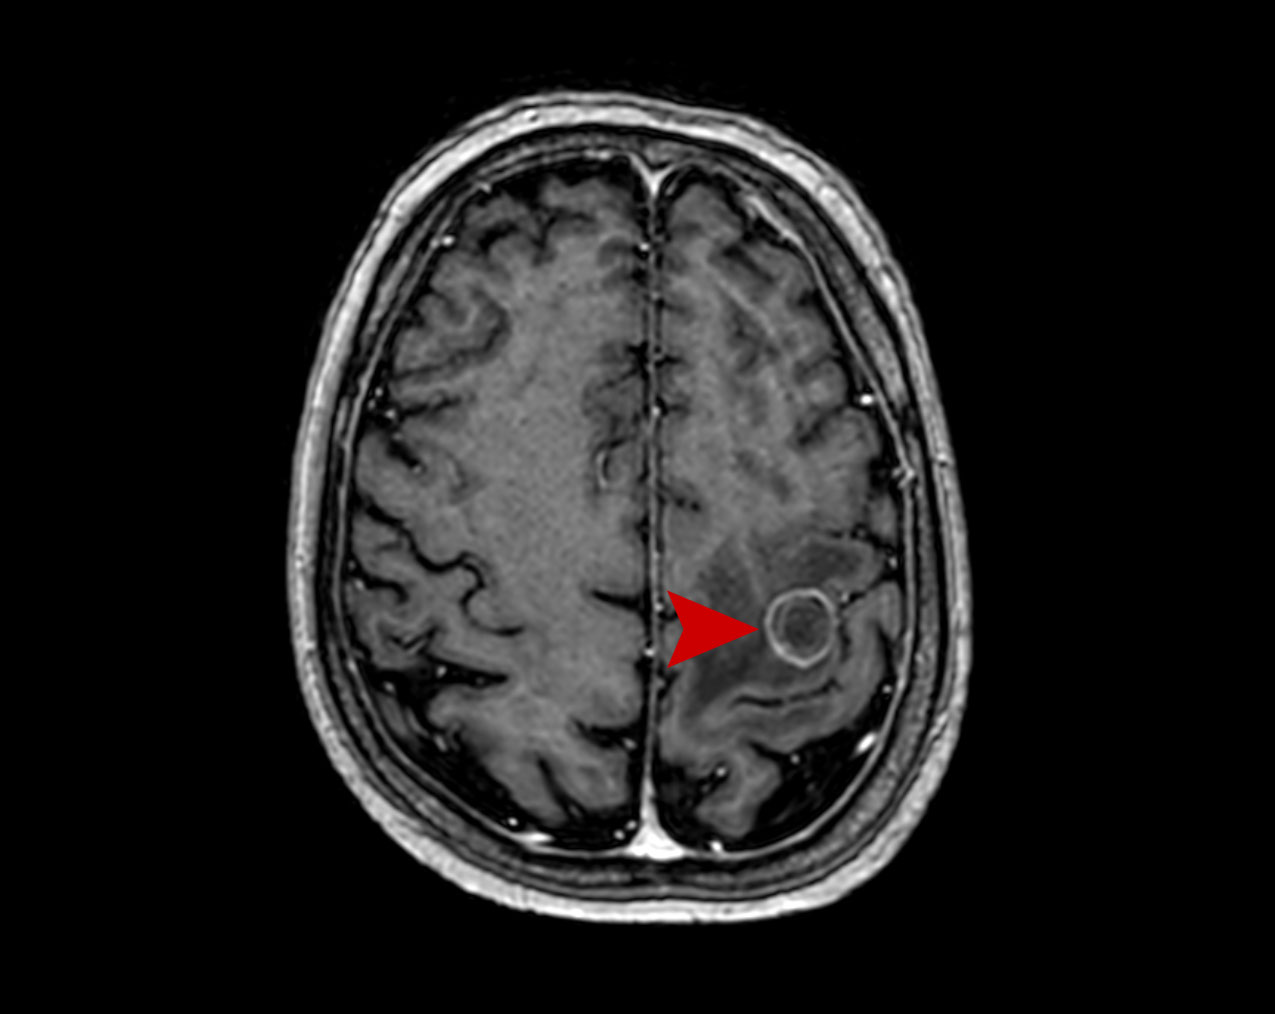

Μετάσταση Καρκίνος Πνεύμονα Θεραπεία με CyberKnife #15

Άρρεν 54 ετών με εγκεφαλική μετάσταση από Ca πνεύμονα αριστερά μετωπιαία. Σύγκριση MRI 5/2021 με…